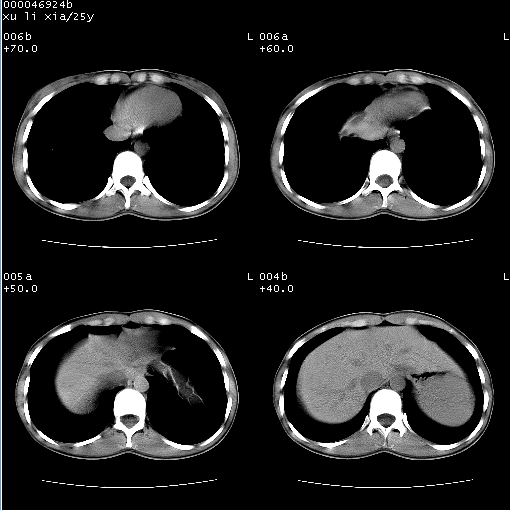

患者 女,25岁。因“左侧卵巢肿瘤”术前胸片偶然发现两肺病变。平素无明显不适,无呼吸系统症状及体征,无传染病史。

盆腔ct扫描(ps+ce)提示:左侧附件区畸胎瘤。

胸部ct轴位平扫(层厚10mm,螺距1.5,重建间隔10mm),图像如下:

(注:上级医院会诊胸部ct片——考虑为肺部真菌感染。)